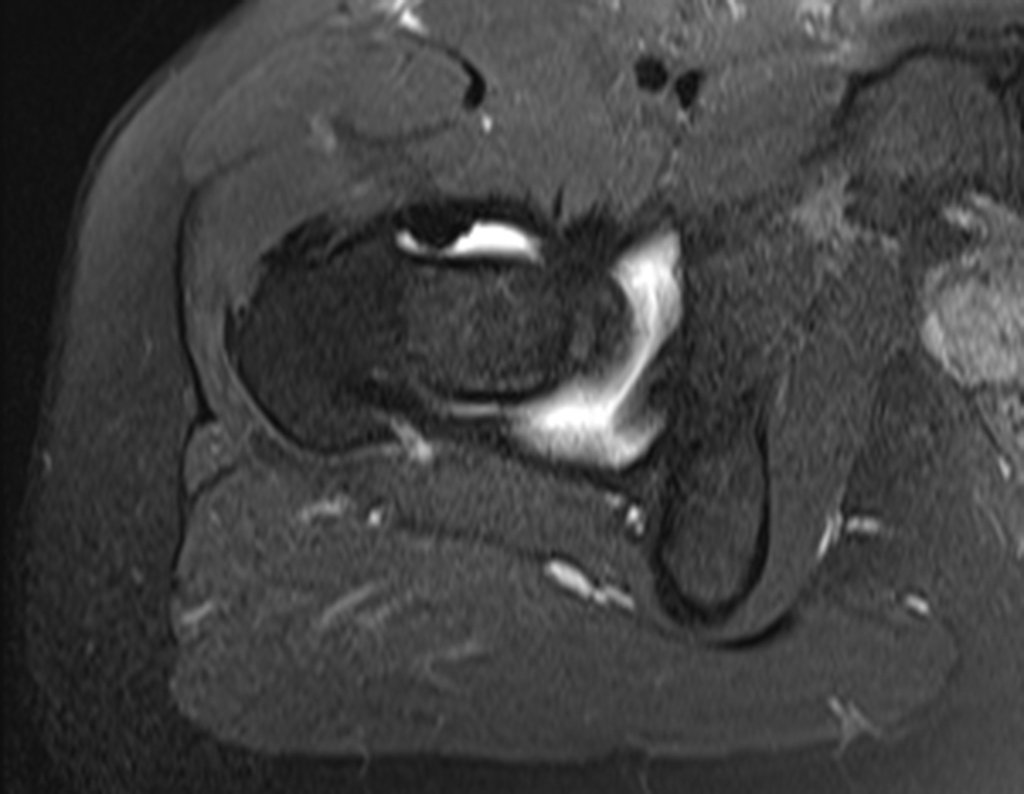

Se le realizó una resonancia magnética de columna lumbar y cadera en abril de 2015, figuras 1 a 8.

El informe de resonancia magnética de ese momento informó la hipótesis diagnóstica de osteoma osteoide.

Sin embargo, después de cuatro meses, en agosto de 2015 se realizó una artrorresonancia que infirió la posibilidad de pinzamiento femoroacetabular, figuras 9 y 10.